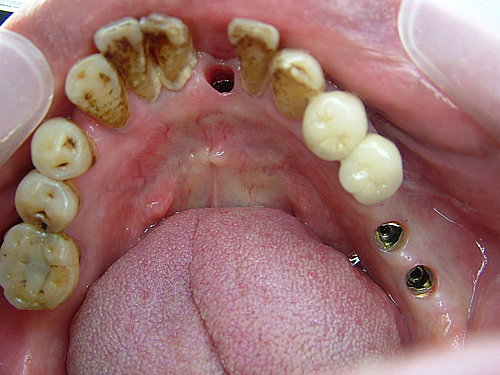

下顎咬合面觀 ..... 右下缺了兩顆大牙 左下只有一顆大牙 咀嚼效率差

牙結石厚 先洗牙清乾淨再說 .....

後牙因條件良好 採不翻瓣一接段植牙術式 (Flapless procedure) ....